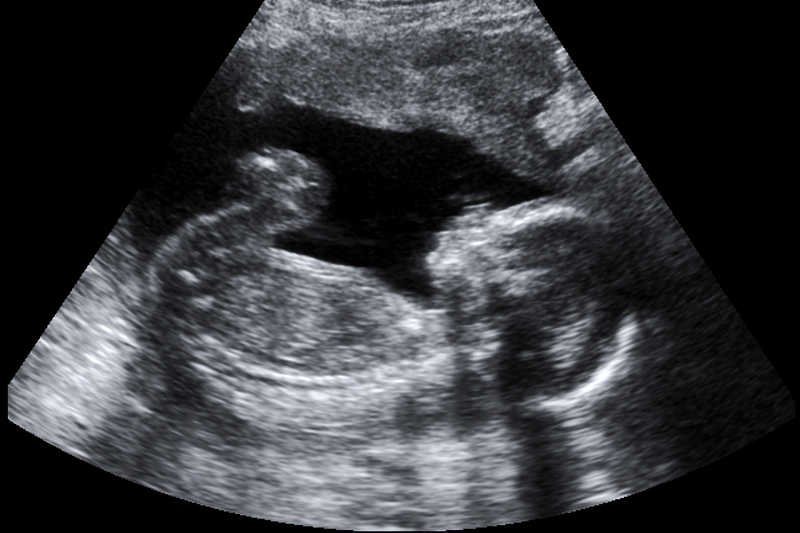

Zdecydowanie mniej respondentów najgorsze zło widzi w obrażaniu uczuć religijnych czy wyśmiewaniu cudzej wiary (39 proc. i 36 proc.). Portal fronda.pl nie kryje oburzenia wynikami badania, gdyż wyraźnie wskazują, że osoby sprzeciwiające się aborcji nie stanowią zbyt dużej siły. Tylko 13 proc. badanych Niemców uważa, że dokonywanie aborcji to łamanie norm w najgorszym ujęciu. "Jeszcze kilkadziesiąt lat temu pewnie większość Niemców uznałaby Dekalog za katalog uniwersalnych wartości. Dziś zdaje się powstawać nowy dekalog wartości ekologicznego Europejczyka" – czytamy na Fronda.pl.

Tomasz Terlikowski jest znanym przeciwnikiem aborcji. Niejednokrotnie jej zwolenników przyrównywał do nazistów, bo w jego opinii działają według tych samych schematów – zakładają, że część ludzi nie jest tak naprawdę ludźmi. W rozmowie z naTemat tłumaczył, że w kwestii aborcji "myślimy językiem".

Myślimy językiem. Jeśli mówimy o aborcji jak o "zabiegu", to łatwo jest powiedzieć, że każdy ma prawo do opieki medycznej. Jeśli napiszemy, że ten zabieg kończy się zabiciem dziecka, sprawa wygląda już inaczej. A jeśli ktoś ma wątpliwości, czy to tak wygląda, to ja go zapytam, czy po aborcji dziecko żyje. CZYTAJ WIĘCEJ